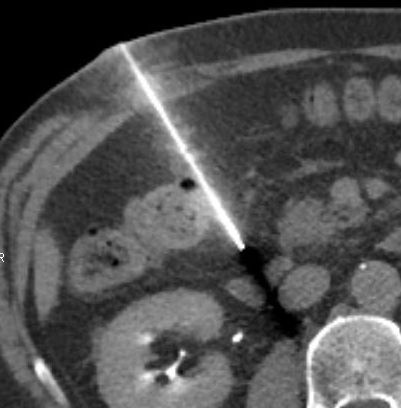

Les thématiques développées seront les biopsies complexes guidées par scanner, les défis des interventions percutanées guidées par tomodensitométrie (par le Pr Eric de Kerviler, Hôpital St-Louis, Paris) et les difficultés d'accès à l'ablation des lésions hépatiques (par le Pr Alban Denys, CHUV Lausanne).